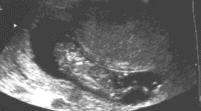

На ультразвуке, черепная коробка симметрично отсутствует. Рудиментарная мозговая ткань покрыта мембраной, а не костью (рис 1-2). Она, как было замечено, выступает над основанием черепа уже вначале второго триместра, и постепенно дегенерирует, пока наконец изображение головы полностью сглаживается позади лицевых структур. Внешний вид лица приобретает подобие лягушки с «выпученными» глазными яблоками (рис 3,4). Сопутствующее многоводие обычно развивается во втором триместре из-за отсутствия или неэффективного эмбрионального глотания (рис. 3). Часто наблюдается повышенная активность эмбриона. Рис.1-4. Сонографические ловушки в диагнозе анэнцефалии обычно возникают вокруг трудностей в визуализации при головном предлежании с глубоким положением головы. Дифференцирование анэнцефалии от серьезной микроцефалии или большого энцефалоцеле может также быть трудно, но при этих состояниях свод черепа всегда присутствует. Связанные с амнионом синдромы, ассоциированные с разрушением головного мозга, могут также имитировать анэнцефалию. Наконец, неопытный сонографист может путать мембрану с нормальным сводом черепа в раннем втором триместре. Поэтому, идентификация эмбриональной головы не исключает анэнцефалии.